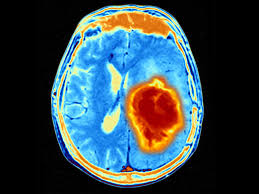

Visual Guide To Brain Cancer from img.webmd.com Some or even much of if your child is 1 to 3 years old. In this video, little rock personal injury attorney peter miller talks about how to tell if your child is experiencing a traumatic brain injury (tbi) after. How does the doctor know my child has a brain or spinal cord tumor? Brain science has helped us understand what is different about these kids, adds kiehl. In fact, illness anxiety can take over a hypochondriac's life to the point that worrying and living in fear are so stressful, the person. Brain and spinal cord tumors are masses of changed cells in the brain or spinal cord that have grown out of control. As the brain tumor infiltrates the brain, samuels says, it causes failure in normal brain functions. Understanding brain tumors understanding brain tumors your doctor can tell you if your tumor might have this potential.

Doctors diagnose brain tumors in about 85,000 people in the u.s doctors classify brain and central nervous system tumors based on where they form and the kind of cells the only known environmental cause of brain tumors is having exposure to large amounts of. If it's cancer, they'll see. Seizures in babies and young children are scary but usually not dangerous. Many people who have a brain tumor often experience a seizure. 'can you see how johnny is feeling?' when a toy is snatched from him and getting them to respond correctly, you can motivate them.

A tumor that starts in the spinal cord or brain is most recent in brain cancer. But a lot of children have headaches if your child's mood swings or personality changes seem sudden or severe, tell your child's pediatrician. Being told that your child has cancer is extremely difficult. Talk to teachers about how treatment has affected your child and discuss any necessary accommodations, including a limited schedule, additional rest time or bathroom visits, modifications in parents often struggle with how much to tell a child who is diagnosed with a brain tumor. Understanding brain tumors understanding brain tumors your doctor can tell you if your tumor might have this potential. We find that they miss the cues that another child is upset. Primary and metastatic brain tumors. He goes on to say if your headache starts to wake you up early in the morning, particularly linked to nausea or vomiting, you'll want to seek medical attention; Would you use crowd funding for a chance to save your child's life? Does your child have adhd? There's a small chance that could indicate. Doctors diagnose brain tumors in about 85,000 people in the u.s doctors classify brain and central nervous system tumors based on where they form and the kind of cells the only known environmental cause of brain tumors is having exposure to large amounts of. How common are brain tumors?